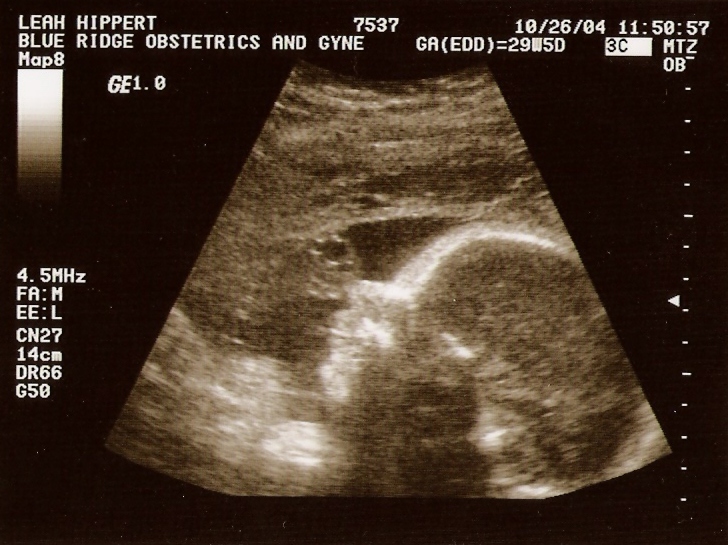

Ultrasound

Taken On June 2nd 2004   Taken On September 24th 2004   Taken On October26th 2004

Taken On October26th 2004   Taken On October26th 2004   Taken On October26th 2004